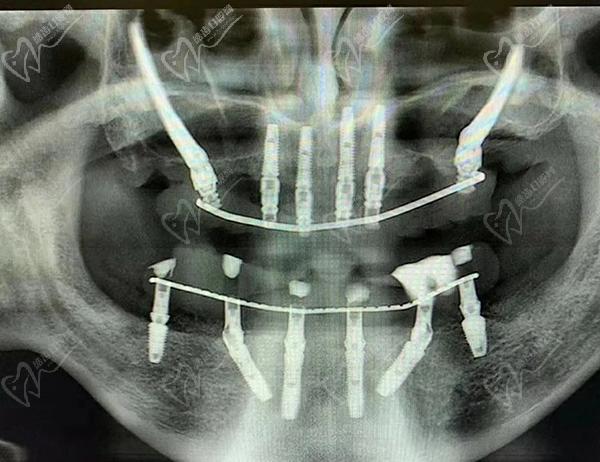

第三步:种植牙

接下来,医生会在必要的位置上植入种植体。这些种植体充当人工牙根,用于支撑和固定新的牙齿。采用数字化智能种植技术,上下牙颌各仅需要4-6颗植体就能恢复半口牙14颗牙齿。